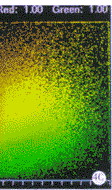

2.2 无共存 图3a显示了一些双标细胞,图象用568 nm和488 nm氩/氪激光激发,同时采集. 从图象可看出,绿色荧光图象的细胞核中有一些红色荧光重叠渗透(bleed-through). 如不去除这种重叠,即进行共存分析,将产生错误. 因此在图3b通过在红色图象中选择一个测量值255和从绿色图象中选择一个测量值208加以去除. 图3b, 3c可看出两者的共存系数如实际情况所示是0.00.

图3a 免疫荧光双标记胃粘膜上皮细胞以及复合图象,红色为细胞核(TR 标记),绿色为细胞质(FITC标记).

图3b 共存分析对话框显示双标物质共存系数是Red=0.00;Green=0.00

图3c 共存分析对话框显示双标物质共存系数是Red=0.00;Green=0.00